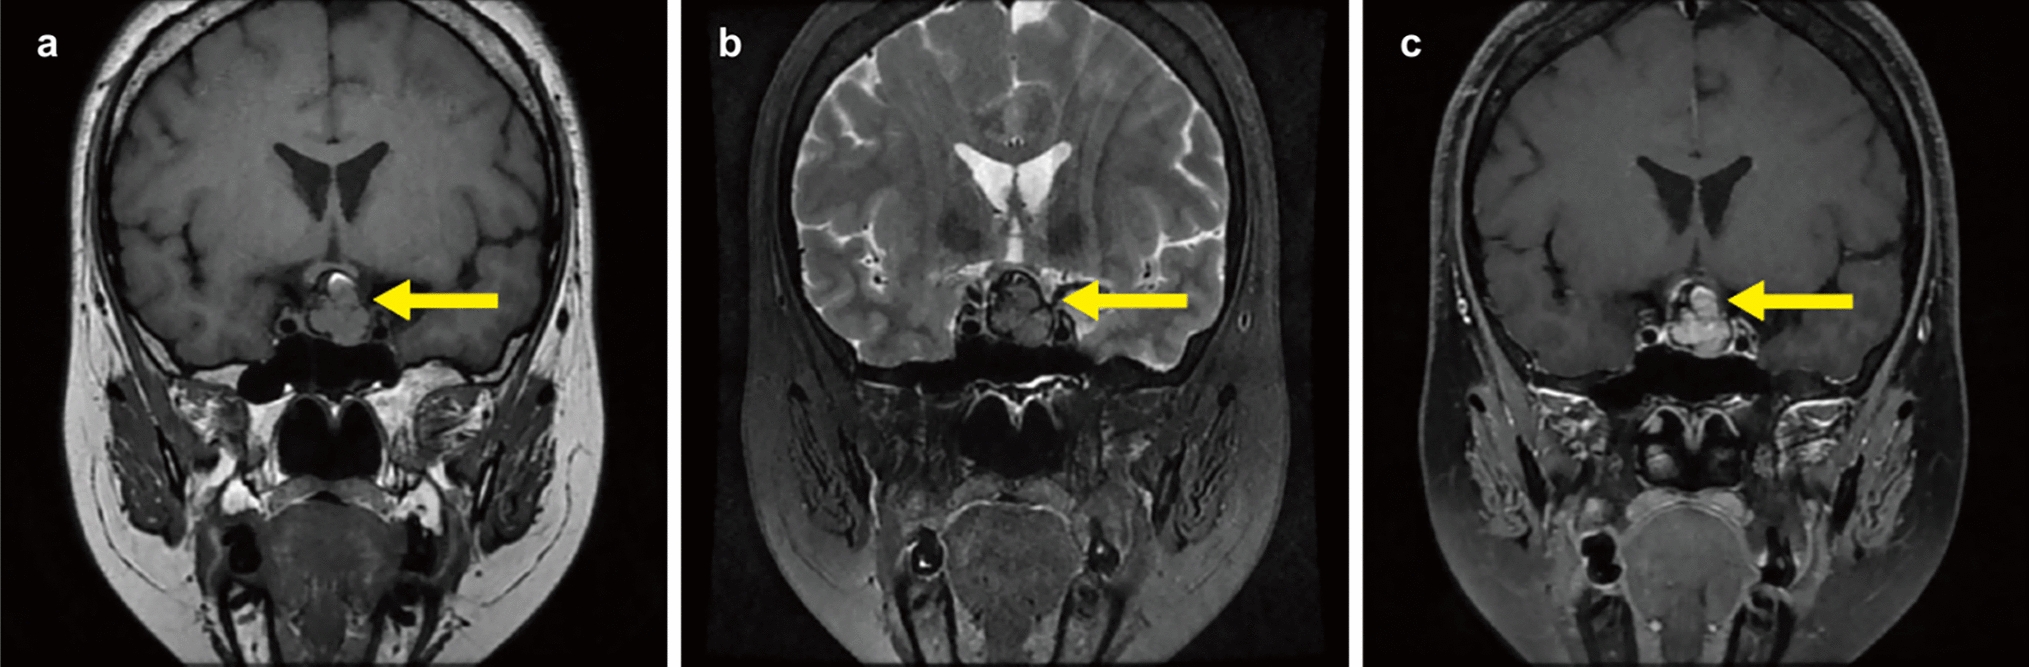

Donoho D, Zada G (2015) Imaging of central neurocytomas. Neurosurg Clin N Am 26:11–19. https://doi.org/10.1016/j.nec.2014.09.012

Ramsahye H, He H, Feng X, Li S, Xiong J (2013) Central neurocytoma: radiological and clinico-pathological findings in 18 patients and one additional MRS case. J Neuroradiol 40:101–111. https://doi.org/10.1016/j.neurad.2012.05.007